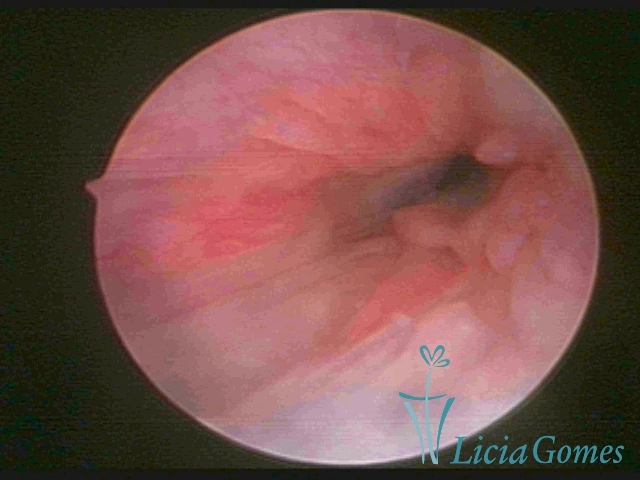

Primeira porção ou setor proximal ou setor inferior:

Durante a fase proliferativa, encontramos muco claro e cristalino pouco aderente à óptica. As criptas e as papilas apresentam-se um pouco edemaciadas e vascularizadas, micro vesicular, lembrando cachos de uva.